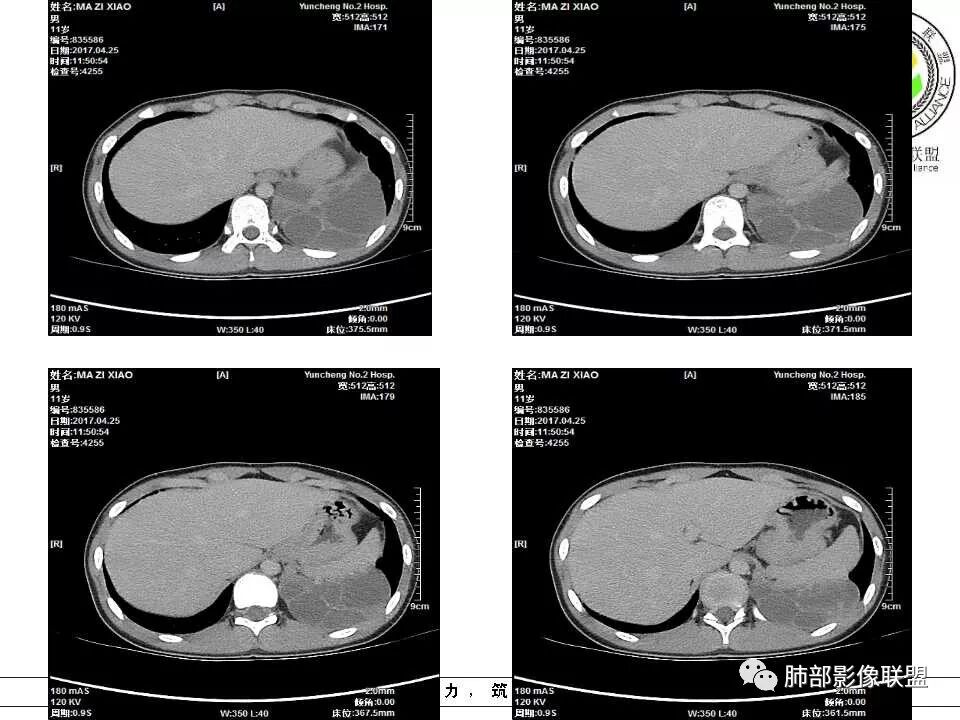

病例提供:运城市第二医院  王崇军

肺隔离症,供血动脉来源腹主动脉

肺隔离症 膈下腹主动脉供血 肺静脉引流 多房改变支气管扩张积液?

左下肺囊性占位,多发分隔,增强分隔及边缘强化,腹主动脉供血,考虑肺隔离征。

左下叶基底段,实性,囊性变,体动脉供血,支持隔离

腹主动脉供血,肺隔离症

儿童左下肺囊性占位,多发分隔,增强分隔可见强化,腹主动脉供血,肺隔离征。

电话随访,患者在西安某医院手术,为肺隔离症,供血两支动脉,均来自腹主动脉,引流入肺静脉。